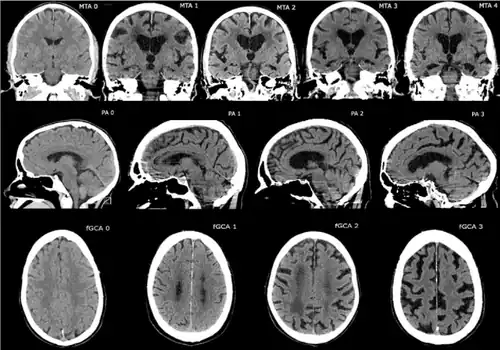

Brain images

Computer tomographies of medial temporal lobe, posterior atrophy and frontal cortical atrophy. Superagers usually show less cortical atrophy.[155]

A superager (also super-ager) is a person of advanced biological age (80 years or older)[156] who retains the cognitive performance of a much younger person.[157] The term was coined by the neurologist Marsel Mesulam.[157] Individuals of this range of age who show normal performance are called "typical-agers" to differentiate them from superagers.[155]